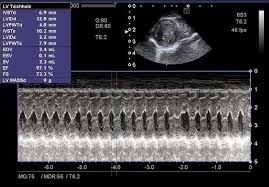

심장 초음파는 초음파를 이용해 심장의 크기, 움직임, 판막 상태, 혈액 흐름을 실시간으로 관찰하는 검사입니다. 방사선 노출이 없고 통증도 거의 없어 반복 검사에도 부담이 없습니다. 특히 심장 질환이 의심될 때 가장 기본적으로 시행되는 검사로, 심장 초음파로 알 수 있는 병의 범위는 생각보다 매우 넓습니다.

심부전은 심장이 혈액을 충분히 펌프질하지 못하는 상태입니다. 심장 초음파를 통해 심장의 수축력(박출률)을 측정함으로써 심부전 여부를 확인할 수 있습니다. 호흡곤란, 쉽게 피로해지는 증상이 있다면 심장 초음파로 알 수 있는 병 중 가장 먼저 확인해야 할 질환입니다.